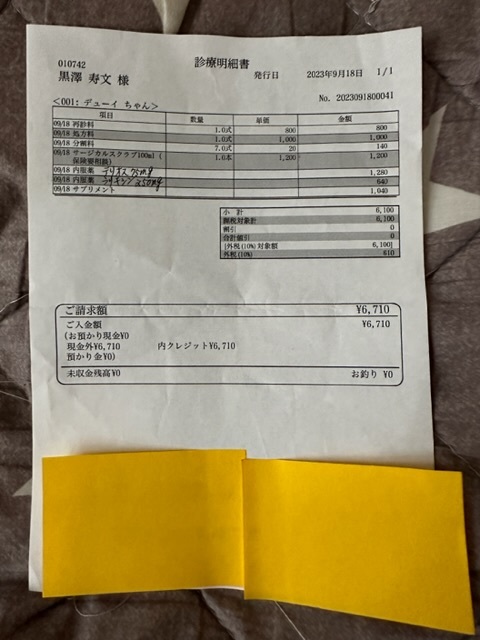

実際にかかった治療費

★

★

★

★

▶︎ 4. 掲載している資料について

ページ上に掲載している診断書や診療明細書などの資料は全て動物病院から掲載の許諾を得ております。